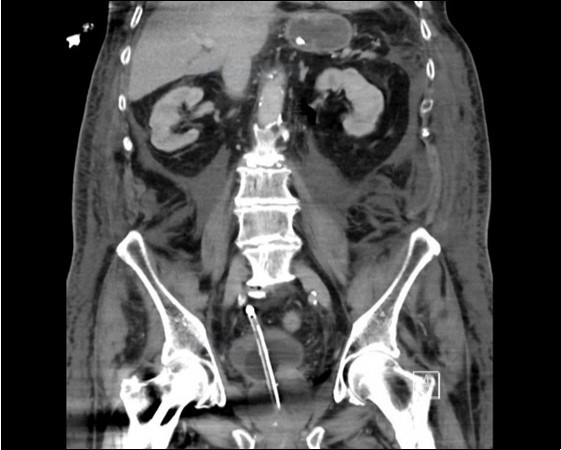

His irrigation circuit-chart showed he had received 10 litres Normal Saline via the afferent limb, but only 3 litres recorded at the efferent limb. It was suspected the catheter was adjacent to a vascular-cystic interface, however an urgent contrast CT revealed the irrigating catheter perforating the bladder, being situated in the abdominal cavity (see 3 images). His arterial blood-gas analysis demonstrated the expected normal anion-gap academia, however his Strong Ion Difference calculations, sodium-chloride difference of 13 and a normal albumin level, perfectly demonstrated the expected calculated BE of -13. The catheter was withdrawn, and the patient made a full recovery.

An urgent CT abdomen revealed a bladder perforation with the tip of the irrigating catheter situated in the abdominal cavity (Figure 1, Figure 2, Figure 3a,Figure 3b). This was most likely due to over-insertion of the 3-way catheter due to the extra force required because of the benign prostatic hypertrophy. He had therefore been receiving normal saline as ‘peritoneal dialysis’ with normal saline since insertion of the catheter. The catheter was withdrawn, and the patient made a full recovery.

Figure 2.coronal plane CT image